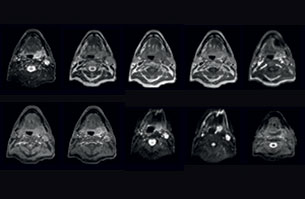

Visualizing critical structures with MRI before prostate radiation therapy

A 63-year-old patient with prostate cancer, cT3bNxM, Gleason 7, underwent MRI on Ingenia 3.0T MR-RT before radiation therapy.

Intraprostatic lesions are visible on the bTFE MR image, but not on the CT image. MRI shows excellent soft-tissue contrast for the visualization of critical structures like the rectum and penile bulb.

Fiducial markers (green arrows) are used in registration of MR images to CT, to transfer the MR-based delineations onto the CT image dataset.